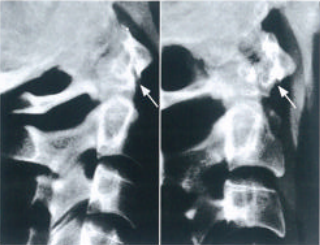

• A型:寰枢关节前方不稳定(图10)。

图10 寰枢关节前方不稳定:颈部后伸时衰椎复位,而颈部屈曲时,寰椎向前移位,寰齿间隙增大

A型:寰枢关节前方不稳定受伤机制(图10)为屈曲损伤导致的横韧带断裂或撕脱骨折,寰椎前移加大,寰齿间隙可达到5mm (图11)。如果寰椎前移进一步加大,翼状韧带将会受到牵拉。

图11 a.正常寰齿间隙 (星号)成年人为3.5mm,儿童为5mm;b.如果寰齿间隙增大,则横韧带断裂或者撕脱骨折